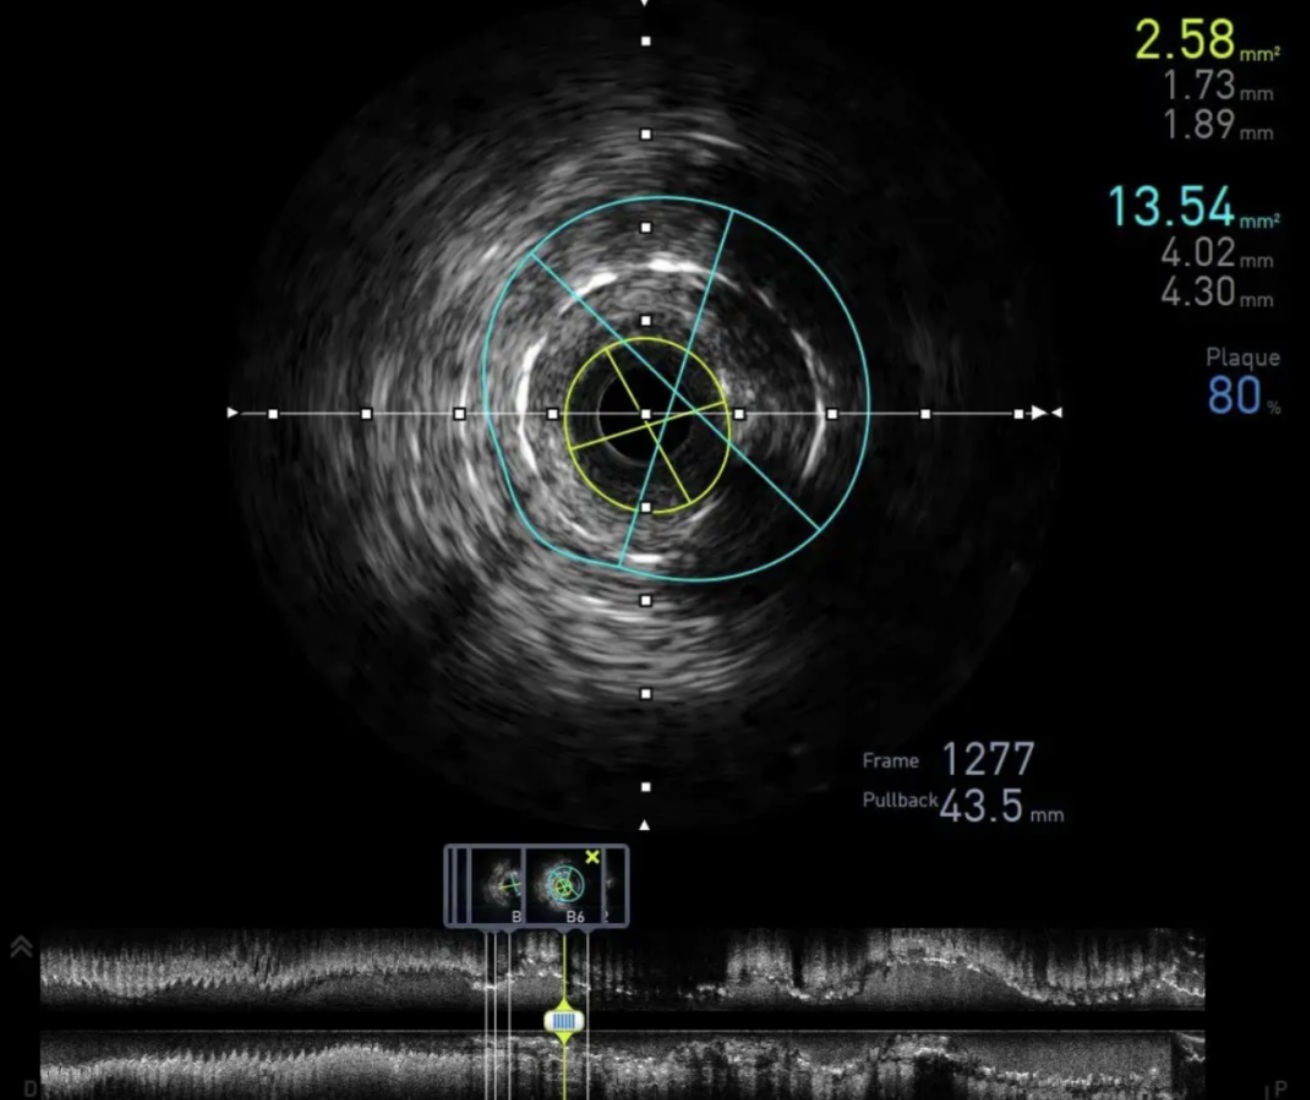

血管内超声(Intravascular ultrasound,IVUS)是精准PCI的主要诊断技术的三个组成部分之一(其它两个分别是血流储备分数(FFR)和光学相干断层扫描(OCT)),是指通过导管技术将微型超声探头送入血管腔内,显示血管横截面图像,从而提供在体血管腔内影像。

简单来说,这是一种血管内的成像方式,在PCI手术中可起到重要的辅助决策作用,包括术前评估及术后优化。

近年来,心血管介入治疗与诊断正向精准化转变。相比于传统的医疗器械,IVUS等创新器械可清晰精确地展示血管腔内的图像、结构、性质等详细信息,更好地指导血管介入手术。